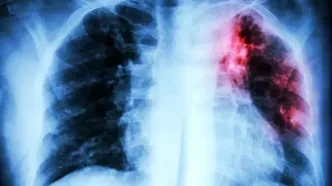

کشندهترین بیماری عفونی جهان معرفی شد

کشندهترین بیماری عفونی جهان اعلام شد